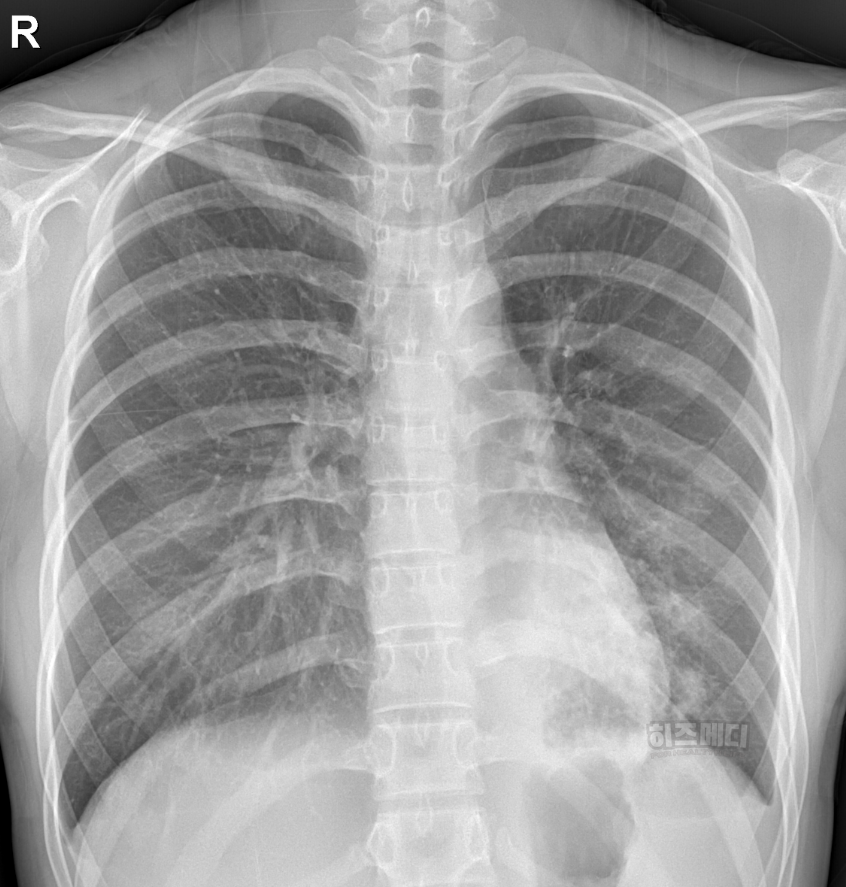

1) 흉부 엑스레이 촬영

폐에 염증이 있는지 확인할 때 흉부 엑스레이를 시행할 수 있습니다. 보통 폐렴으로 발전한 경우, 흉부 엑스레이에서 폐에 하얀 음영이 나타납니다.

마이코플라스마 폐렴은 일반적으로 폐렴의 전형적인 엑스레이 소견과는 다를 때가 많습니다. 폐의 폐포와 혈관사이를 간질이라고 부르는데, 이 부분에 주로 하얀 음영들이 많이 보이게 됩니다.

또한 병변이 양쪽 폐에서 동시에 관찰되는 경우가 종종 나타나며 주로 폐의 하엽에 많이 나타납니다. 미세한 결절이나 그물망 같은 모습으로 나타나기도 합니다.

마이코플라스마 폐렴은 엑스레이 사진에서는 병변이 심하지 않은데도 증상을 심하게 호소하는 경우가 있으며, 반대로 엑스레이 소견은 심해 보이는데 증상은 경미한 경우도 흔합니다. 따라서 마이코플라스마 감염을 확진하기 위해서는 임상 증상과 혈액검사 등의 종합적인 평가가 필요합니다.